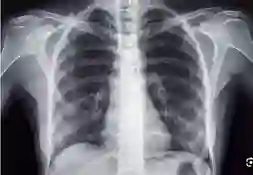

Retrieving visual and textual information from medical literature and hospital records can enhance diagnostic accuracy for clinical image interpretation. However, multimodal retrieval-augmented diagnosis is highly challenging. We explore a lightweight mechanism for enhancing diagnostic performance of retrieval-augmented LVLMs. We train a lightweight LVLM-aware multimodal retriever, such that the retriever learns to return images and texts that guide the LVLM toward correct predictions. In our low-resource setting, we perform only lightweight fine-tuning with small amounts of data, and use only general-purpose backbone models, achieving competitive results in clinical classification and VQA tasks compared to medically pre-trained models with extensive training. In a novel analysis, we highlight a previously unexplored class of errors that we term inconsistent retrieval predictions: cases where different top-retrieved images yield different predictions for the same target. We find that these cases are challenging for all models, even for non-retrieval models, and that our retrieval optimization mechanism significantly improves these cases over standard RAG. However, our analysis also sheds light on gaps in the ability of LVLMs to utilize retrieved information for clinical predictions. Code and models available at: https://github.com/Nirmaz/JOMED.